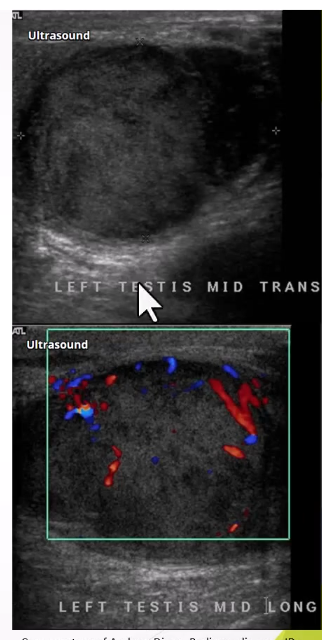

Ultrasound Appearance: Homogeneous intratesticular mass, well-circumscribed with lobulated margins, internal vascularity

Non-seminomas: Occur mainly in younger patients, more aggressive, and metastasize frequently.

Clinical Presentation: Similar to seminomas with potential for metastasis.

Ultrasound Appearance: More heterogeneous with cystic areas or calcification.